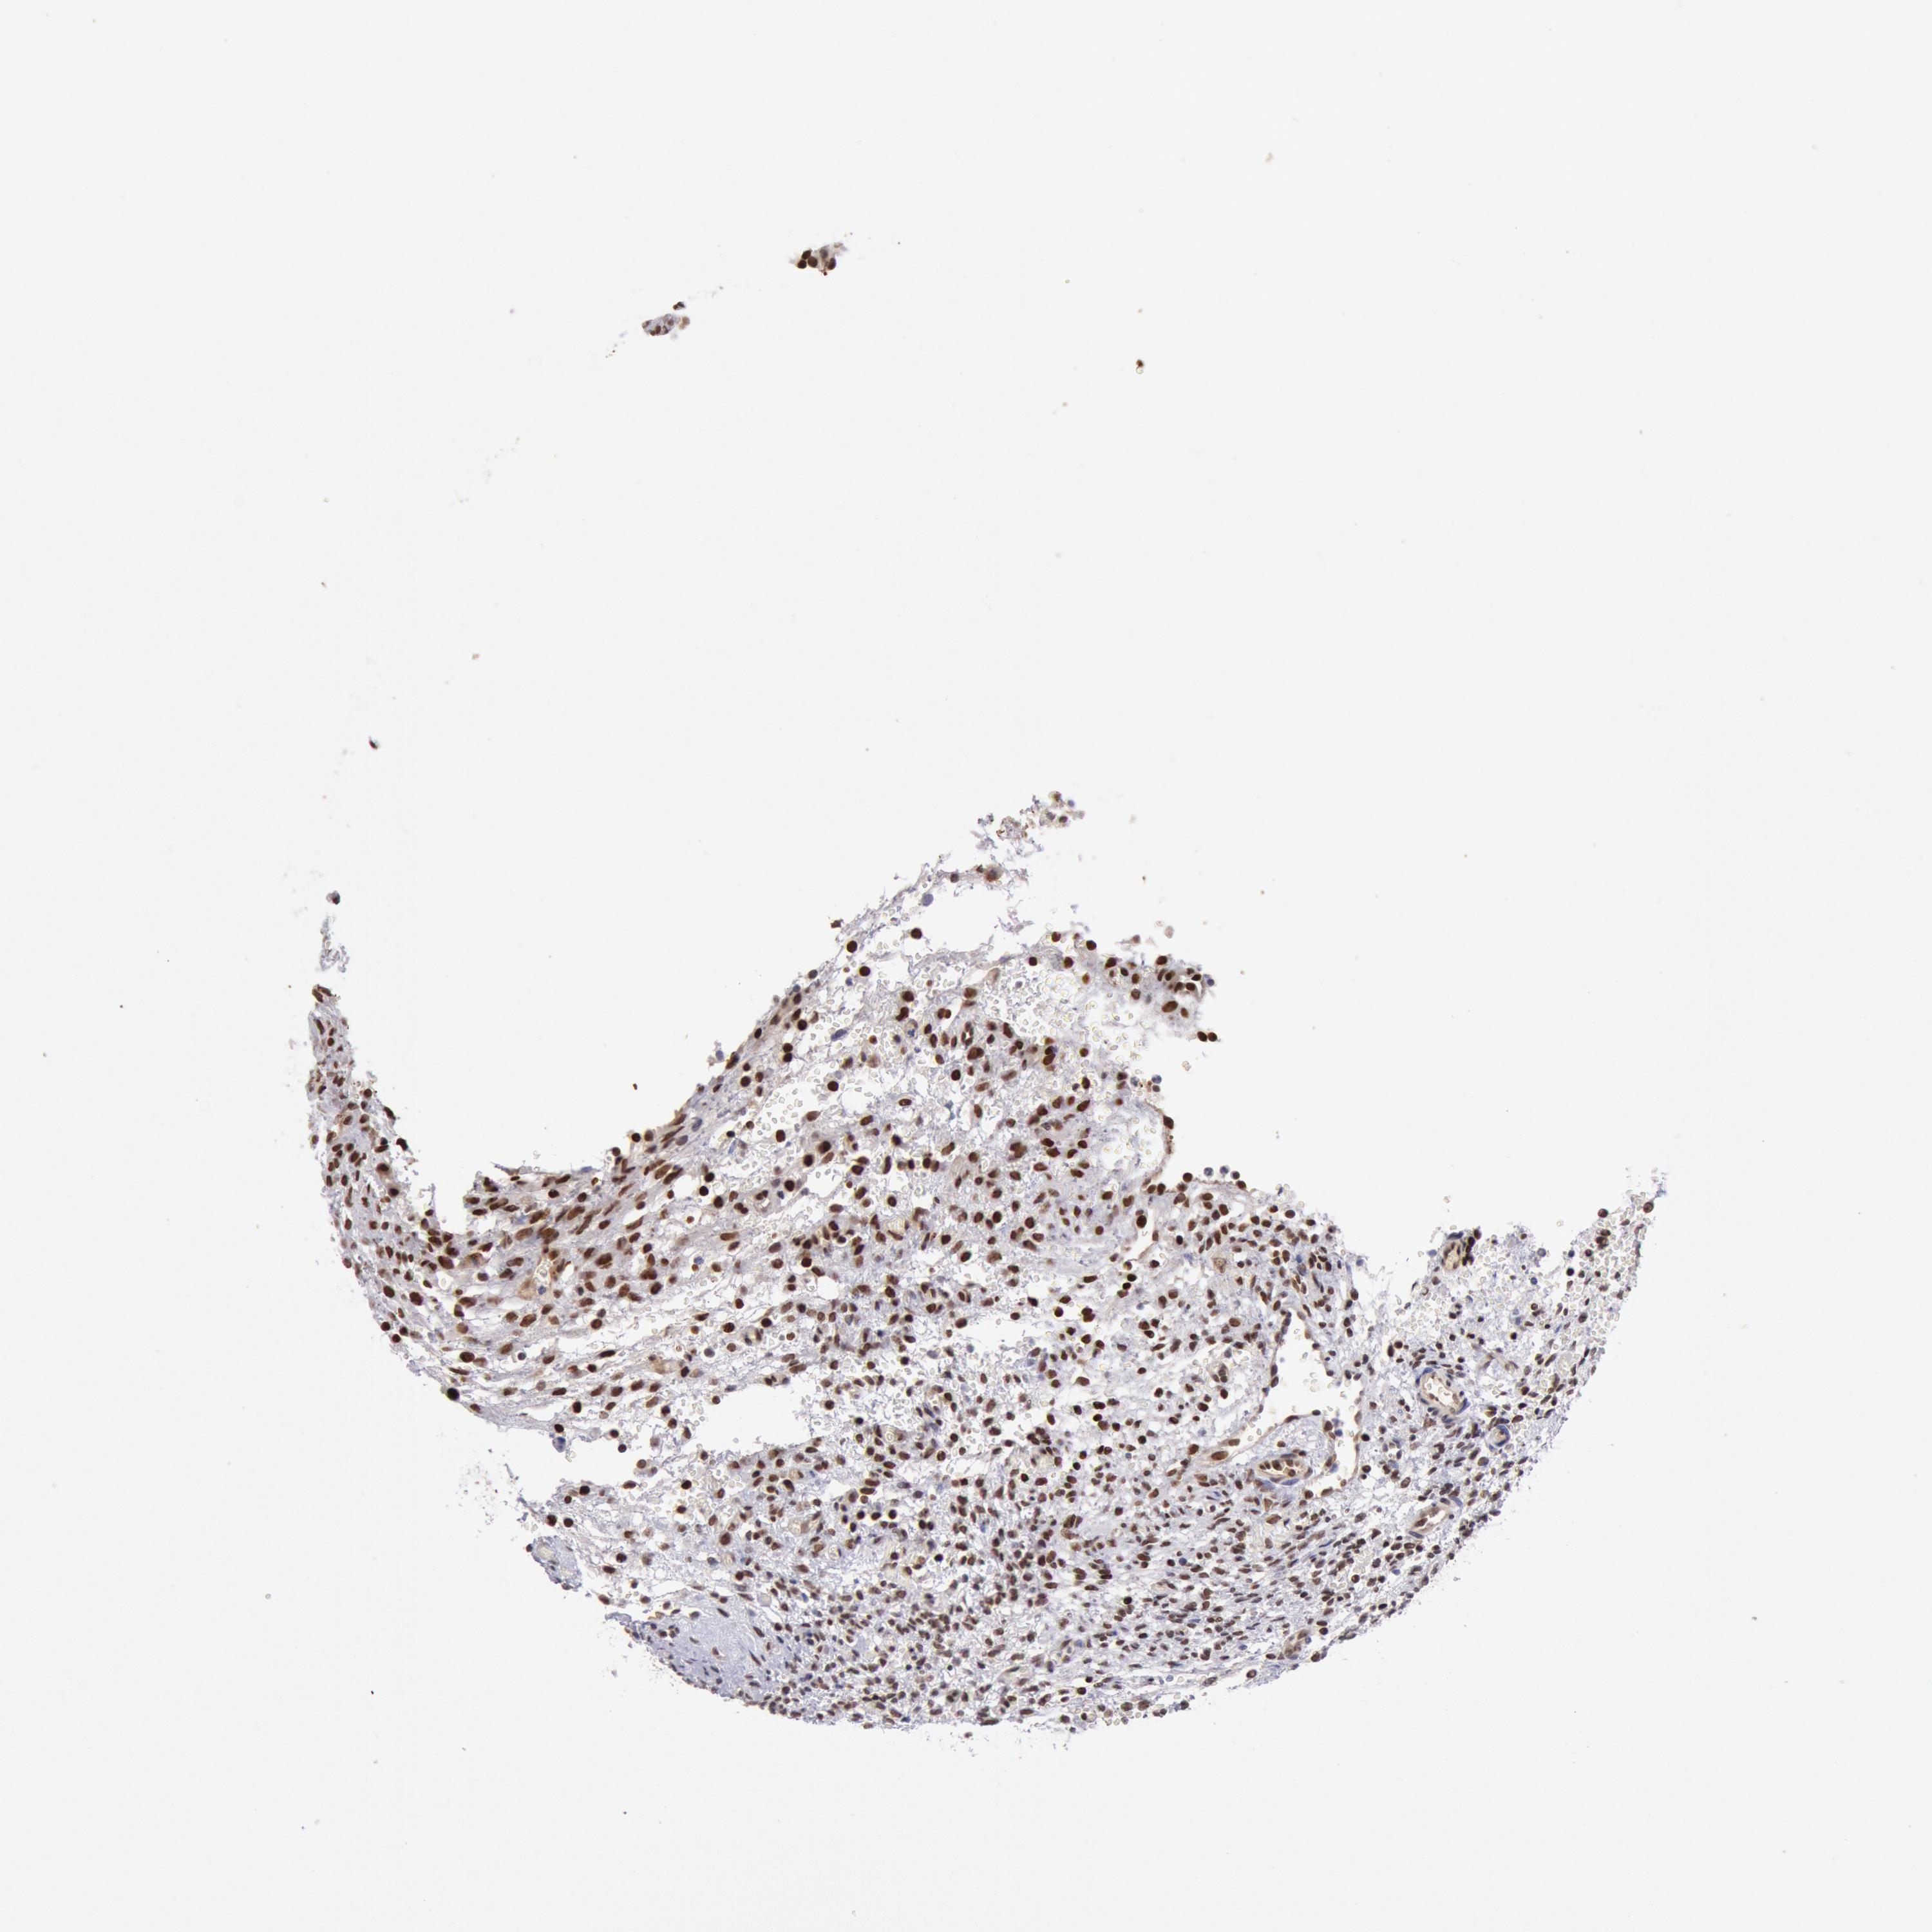

CDKN2B